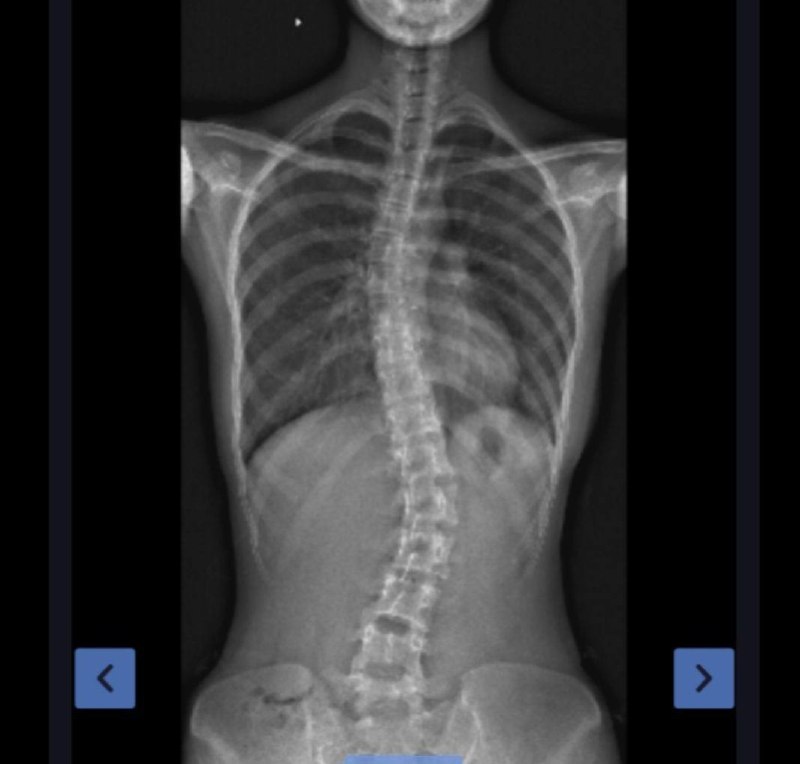

s型身材 露骨 照片 #内在美